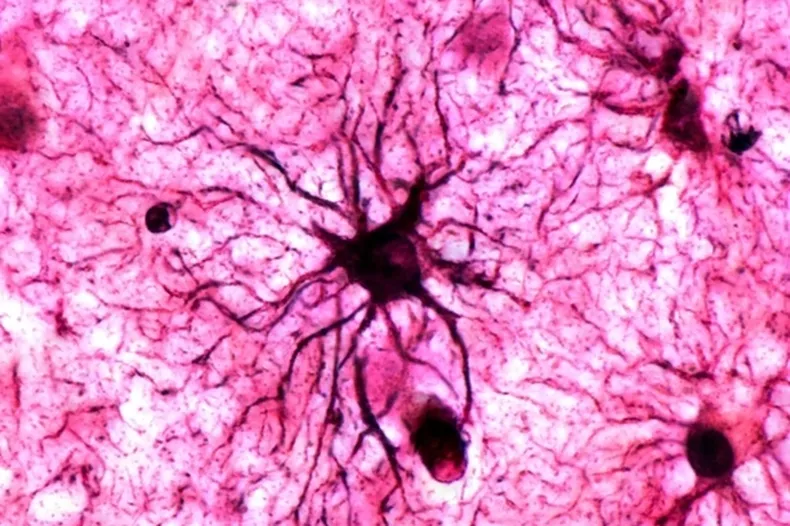

Долгосрочную память сохраняют не только нейроны, но и астроциты